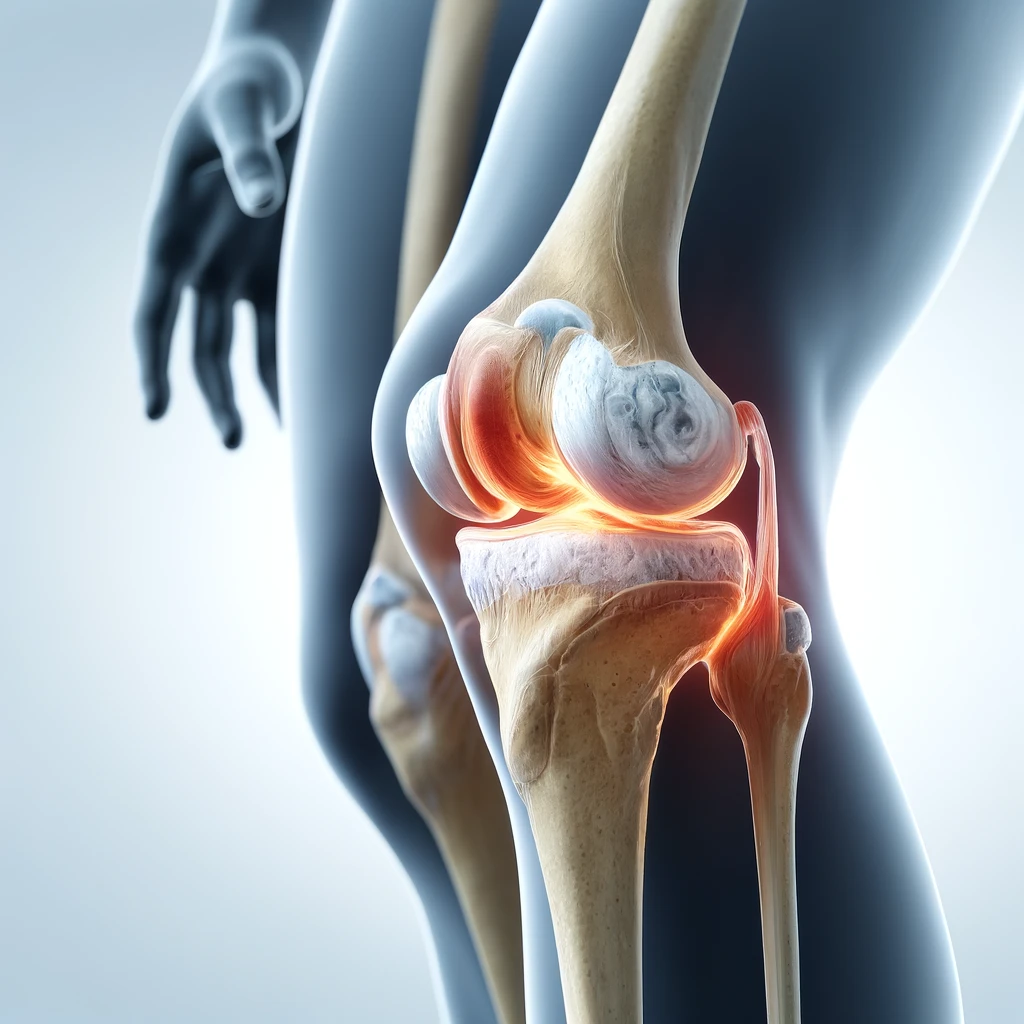

آرتروسکوپی زانو

آرتروز زانوچیست؟ از کجا بفهمیم آرتروز داریم؟ و راه‌های درمان آن را بدانیم.

تعویض مفصل زانو

تعویض مفصل راه‌حلی برای درد شدید و بهبود حرکت با جایگزینی مفاصل آسیب‌دیده است.